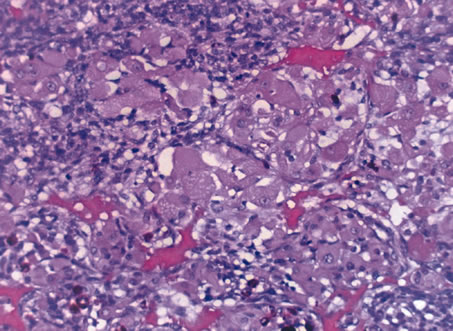

Inflammatory conditions may also lead to iris nodules. Patients suffering from fungal endophthalmitis may demonstrate an irregular yellow-white mass on the iris. Histologically, these appear as necrotizing granulomas containing mycotic agents (Fig. 2). In juvenile xanthogranuloma, a yellowish-gray iris lesion may be associated with spontaneous hyphema, and histopathologically the nodules demonstrate diffuse histiocytic infiltrate (Fig. 3). Multinucleated giant cells displaying peripheral foamy cytoplasm are also noted; these cells are known as Touton giant cells.29 The giant cells and the histiocytes contain lipid that can be demonstrated by oil red O stain.

Fig. 2. Coccidioidomycosis. Iris stroma shows necrotizing granuloma containing mycotic organisms. The organisms show features of Coccidioides immitis. (Hemotoxylin-eosin ×60.)